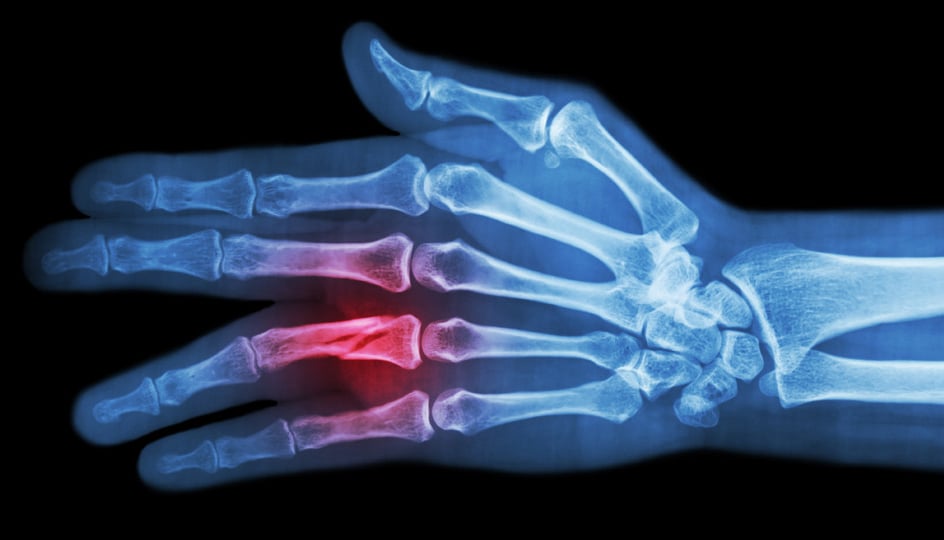

X-ray Showing a Phalanx Fracture

A Phalanx fracture is a break or crack in one of the bones (or phalanges) of your fingers. Each finger has three phalanges — proximal, middle and distal. The thumb has two. These fractures are among the most common hand injuries. They can result from everyday accidents like crushing your finger in a car door, taking a hit during a contact sport, or losing your balance and falling.